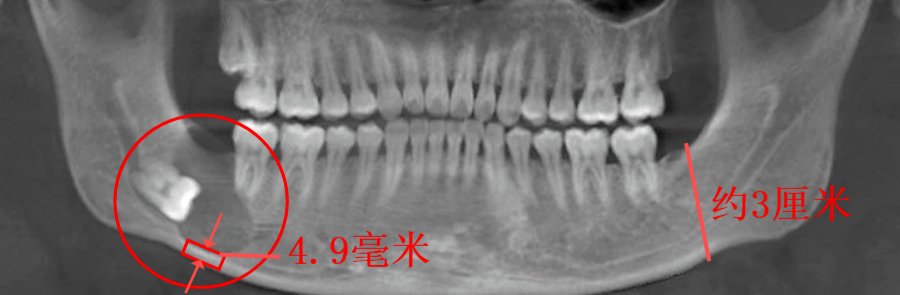

智齿引起下颌骨囊肿(李延超医生提供)

他的这颗智齿不但完全阻生,而且是朝下方“横着长”的,位置藏得很深。智齿周围的牙囊膨胀形变,不断增生分泌物质,下颌骨受压造成骨质吸收,

形成了一个2.5cm*2cm,约有鹌鹑蛋大小的囊性病变(颌骨含牙囊肿)。

正常的下颌骨高度应该有3厘米左右,因骨质吸收,现高度仅剩下不到5毫米。